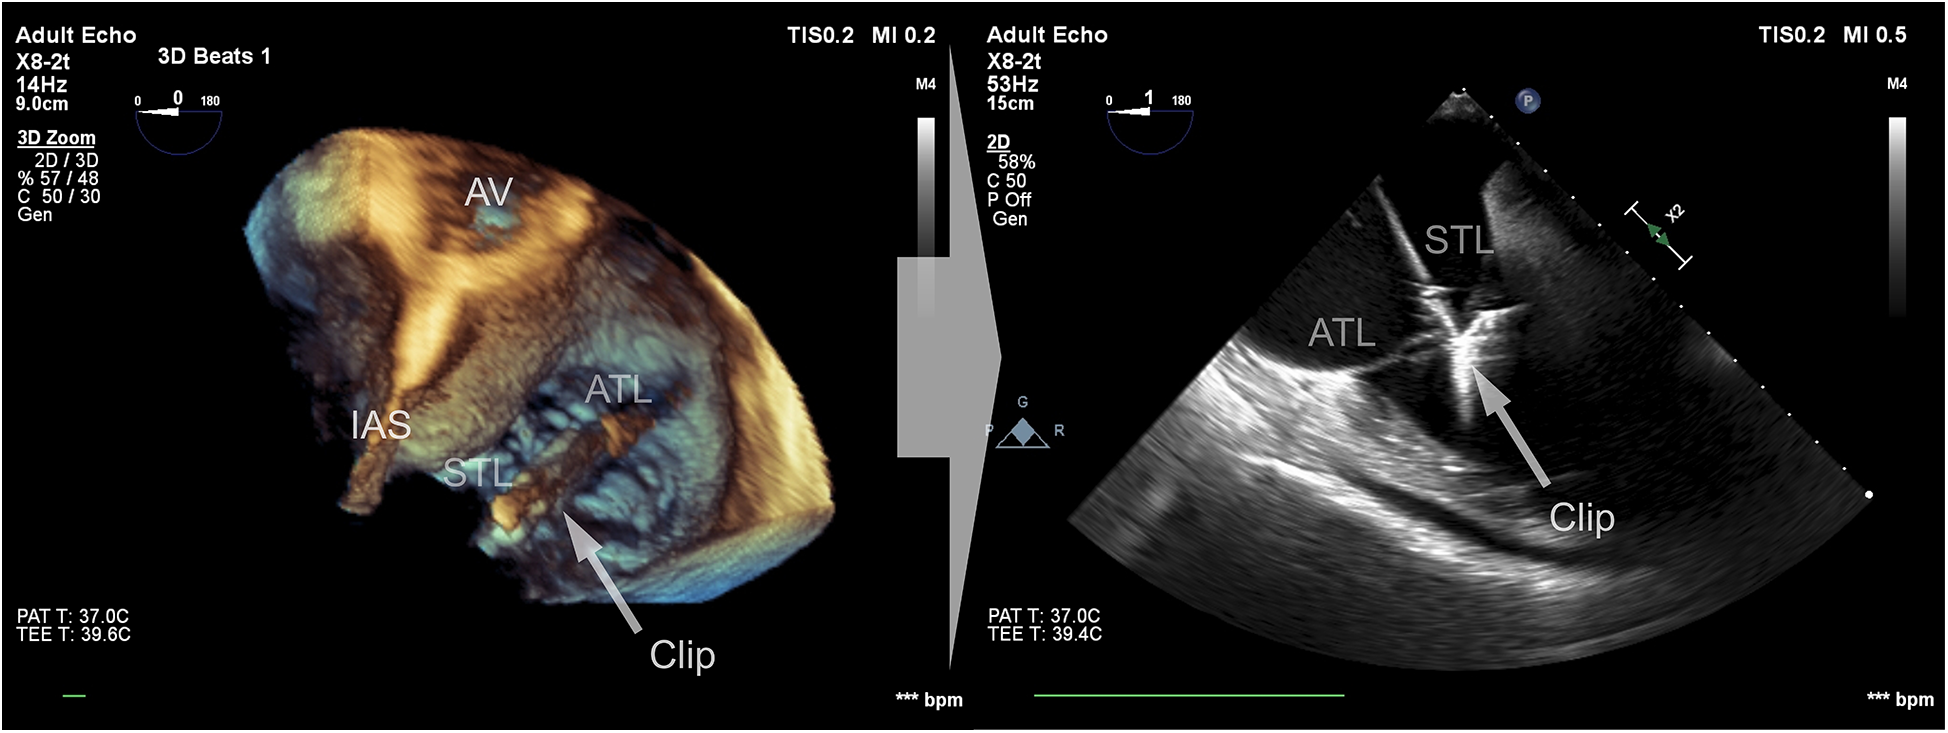

Data were collected using a Philips Epiq CVx rev. 4.0 with a transesophageal x8-2t probe and stored on a Philips Xcelera PACS ver. 3.1. A complete preprocedural echocardiographic assessment of the tricuspid valve was assumed to include the following: (i) an en face planar 3D visualization of the tricuspid valve borders and leaflets during systole to provide spatial orientation during the introduction of a delivery system and device implantation (Figure 1); and (ii) a cross-sectional 2D (inflow–outflow right ventricle) view through the device and leaflet at the implantation point (Figure 2).

Figure 1

En face view of the tricuspid valve in real-time, three-dimensional transesophageal echocardiography. Visualization of sufficient quality for transcatheter tricuspid valve repair guidance includes the components of the valve: (i) annulus; (ii) septal, anterior, posterior leaflets; (iii) fragments of the subvalvular apparatus and anatomical landmarks: (iv) fragment of the aortic valve annulus, (v) fragment of the intra-atrial septum, and (vi) vena cava superior.

Figure 2

Cross-sectional 2D view of the device and leaflets at the point of implantation based on a 3D view after confirming the perpendicularity between the device and the leaflets.